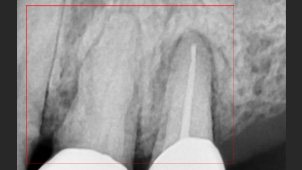

뿌리에 염증으로 흔들리는 치아

잇몸 염증으로 치조골 손실이 많은 상태

심한 염증으로 치아가 흔들리는 상태